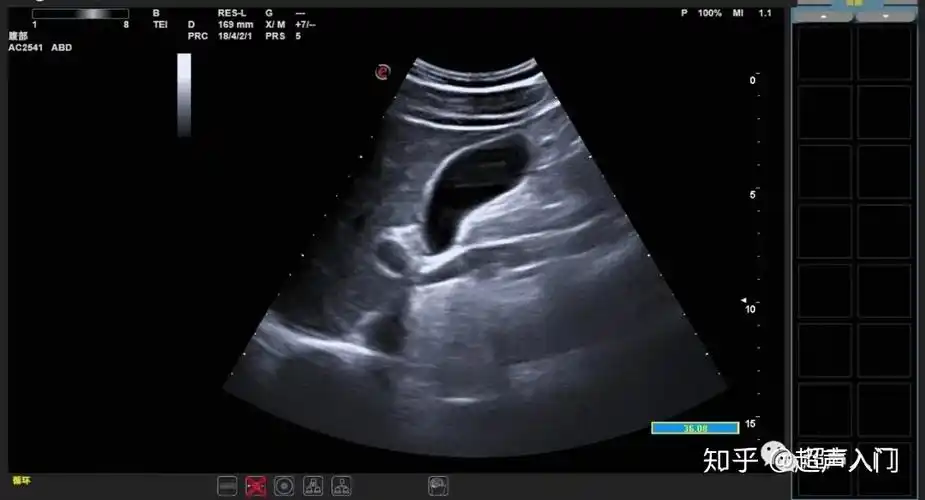

超声知识胆囊的常见疾病的超声诊断

超声入门:急,慢性胆囊炎超声如何诊断?

【胆囊】胆囊典型病例传一发 - 超声医学讨论版 - 专业医生社区,医学

典型胆结石图片 - 超声医学讨论版 - 爱爱医医学论坛